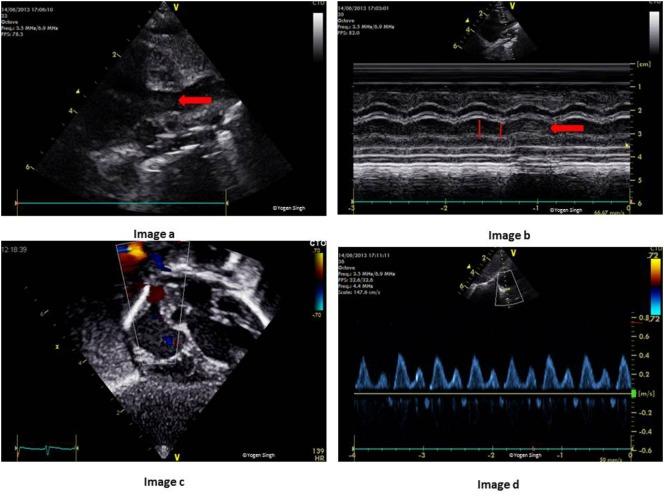

Hemodynamic instability and inadequate cardiac performance are common in critically ill children. The clinical assessment of hemodynamic status is reliant upon physical examination supported by the clinical signs such as heart rate, blood pressure, capillary refill time, and measurement of the urine output and serum lactate. Unfortunately, all of these parameters are surrogate markers of cardiovascular well-being and they provide limited direct information regarding the adequacy of blood flow and tissue perfusion. A bedside point-of-care echocardiography can provide real-time hemodynamic information by assessing cardiac function, loading conditions (preload and afterload) and cardiac output. The echocardiography has the ability to provide longitudinal functional assessment in real time, which makes it an ideal tool for monitoring hemodynamic assessment in neonates and children. It is indispensable in the management of patients with shock, pulmonary hypertension, and patent ductus arteriosus. The echocardiography is the gold standard diagnostic tool to assess hemodynamic stability in patients with pericardial effusion, cardiac tamponade, and cardiac abnormalities such as congenital heart defects or valvar disorders. The information from echocardiography can be used to provide targeted treatment in intensive care settings such as need of fluid resuscitation versus inotropic support, choosing appropriate inotrope or vasopressor, and in providing specific interventions such as selective pulmonary vasodilators in pulmonary hypertension. The physiological information gathered from echocardiography may help in making timely, accurate, and appropriate diagnosis and providing specific treatment in sick patients. There is no surprise that use of bedside point-of-care echocardiography is rapidly gaining interest among neonatologists and intensivists, and it is now being used in clinical decision making for patients with hemodynamic instability. Like any other investigation, it has certain limitations and the most important limitation is its intermittent nature. Sometimes acquiring high quality images for precise functional assessment in a ventilated child can be challenging. Therefore, it should be used in conjunction with the existing tools (physical examination and clinical parameters) for hemodynamic assessment while making clinical decisions.

血流动力学不稳定和心脏功能不全在危重症儿童中很常见。血流动力学状态的临床评估依赖于体格检查,并辅以心率、血压、毛细血管再充盈时间等临床体征,以及尿量和血清乳酸的测量。不幸的是,所有这些参数都是心血管健康的替代指标,它们提供的关于血流充足性和组织灌注的直接信息有限。床旁即时超声心动图可以通过评估心脏功能、负荷状态(前负荷和后负荷)和心输出量来提供实时血流动力学信息。超声心动图能够实时提供纵向功能评估,这使其成为监测新生儿和儿童血流动力学评估的理想工具。它在休克、肺动脉高压和动脉导管未闭患者的管理中不可或缺。超声心动图是评估心包积液、心脏压塞以及先天性心脏病或瓣膜疾病等心脏异常患者血流动力学稳定性的金标准诊断工具。超声心动图提供的信息可用于在重症监护环境中进行针对性治疗,如确定是否需要液体复苏还是使用血管活性药物支持、选择合适的血管活性药物或血管加压药,以及在肺动脉高压中提供特定干预措施,如选择性肺血管扩张剂。从超声心动图收集的生理信息可能有助于对患病患者做出及时、准确和适当的诊断并提供特定治疗。毫不奇怪,床旁即时超声心动图的使用在新生儿科医生和重症监护医生中迅速受到关注,现在它正被用于血流动力学不稳定患者的临床决策。与任何其他检查一样,它有一定的局限性,最重要的局限性是其间歇性。有时,在通气的儿童中获取高质量图像以进行精确的功能评估可能具有挑战性。因此,在做出临床决策时,应将其与现有的血流动力学评估工具(体格检查和临床参数)结合使用。